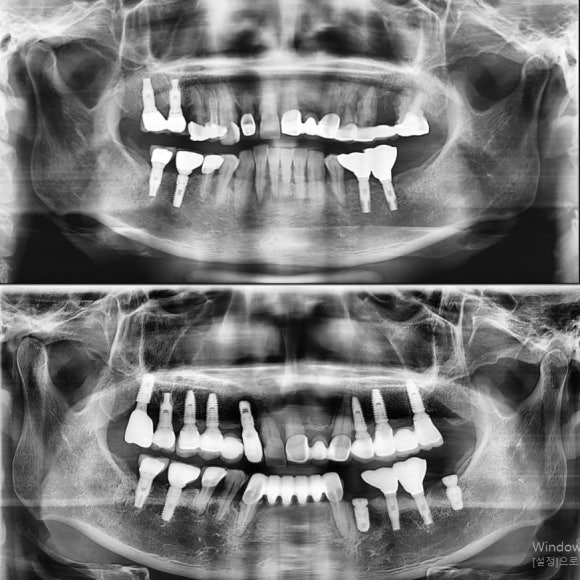

6개에 걸친 임플란트 치료 완료.

사진상 왼쪽은 그나마 시작당시 뼈가 충분하지는 않았지만 임플란트 식립은 가능한 상태여서 2개월만에 끝남.

사진상 오른쪽은 주변 염증이 너무 좋지 않아서 뼈이식과 상악동 수술, 그리고 충분한 치유기간 준 후 6개월만에 보철 들어감.

아래도 점점 치주상태가 나빠져서 임플란트 진행.

머지않아 앞니도 안좋아져서 임플란트 하시러 올 것이라고 예상되는 치아주변조직 상태..